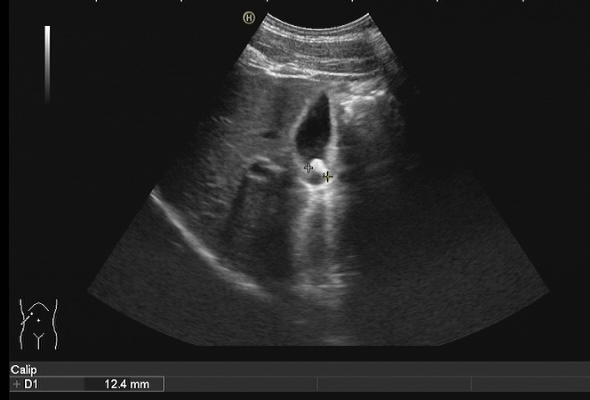

膽結(jié)石診斷方式很多,包括CT、核磁共振膽管造影等方式都可以對(duì)膽結(jié)石進(jìn)行診斷,但是彩超具有無(wú)創(chuàng)、無(wú)、無(wú)輻射、廉價(jià)、快速、可重復(fù)性強(qiáng)等優(yōu)點(diǎn),在臨床上被廣泛應(yīng)用作為膽結(jié)石的首選診斷方式。注意做肝膽彩超檢查必須要空腹,才能準(zhǔn)確檢查出膽結(jié)石哦!

膽囊結(jié)石超聲圖像